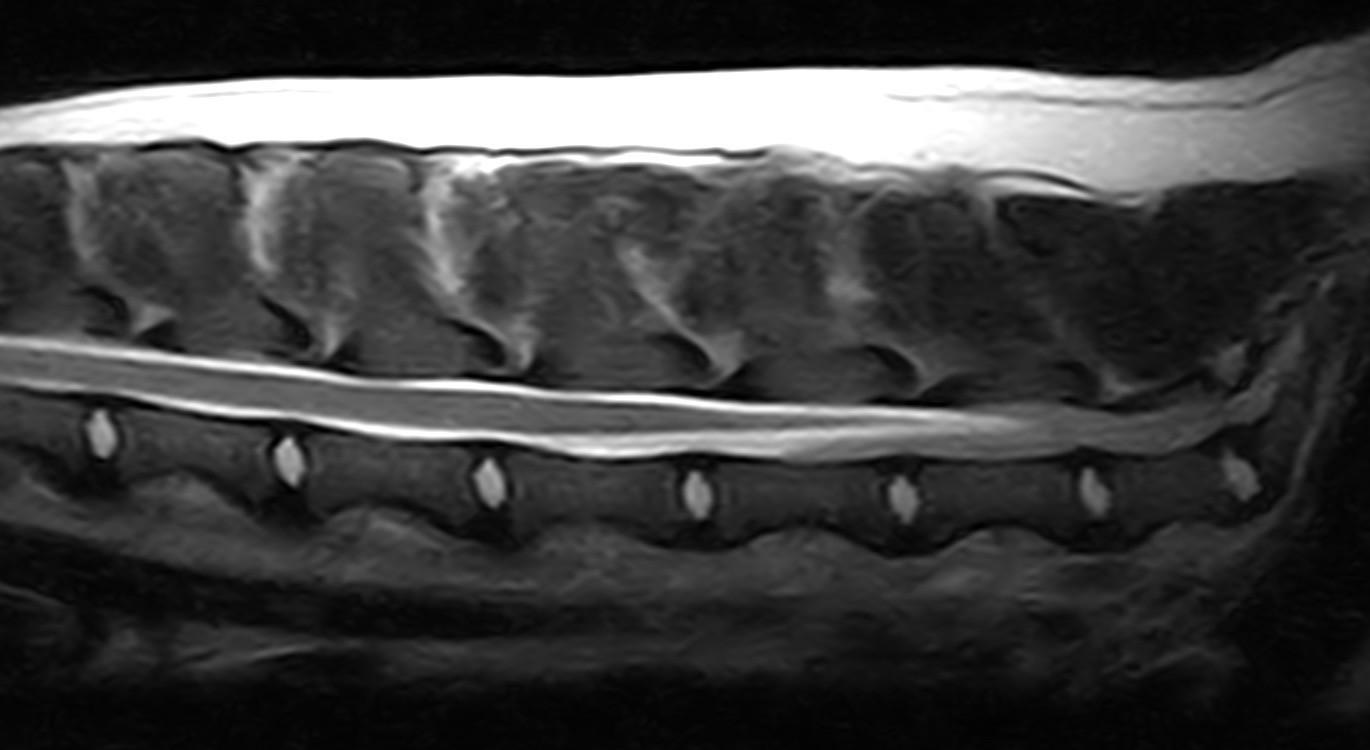

NEST fills a very specific niche in the veterinary community. We provide extremely specialized veterinary care for dogs and cats that have neurological diseases. We have are able to perform MRI scans at our office, perform spinal taps, and neurosurgeries.